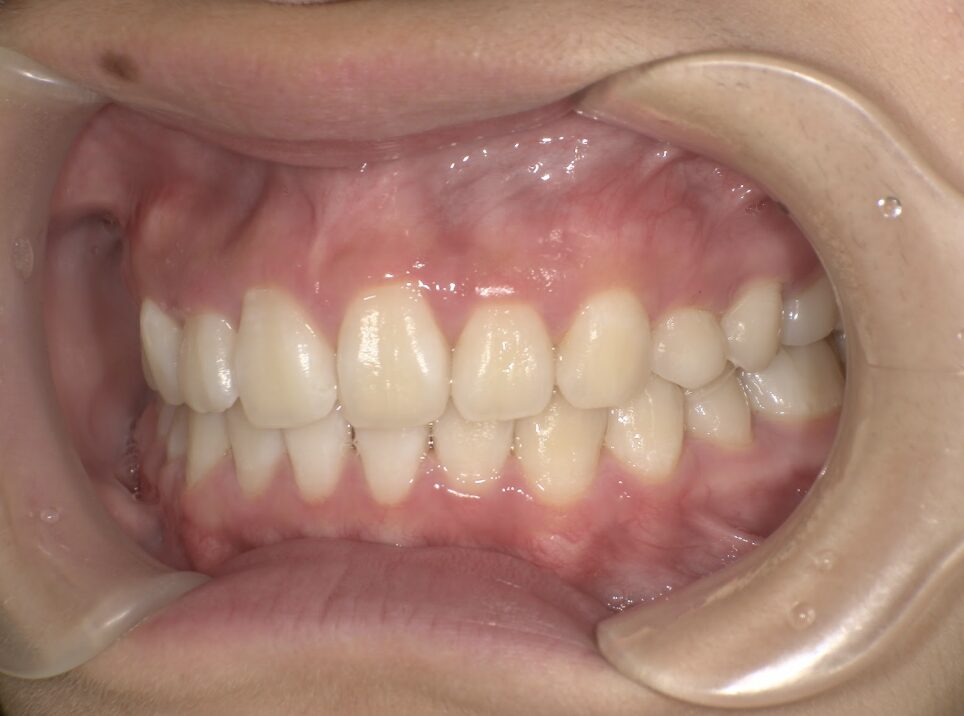

クロスバイト

治療前

ガタガタを主訴に当院を受診され、右上2番にクロスバイトを認めました。IPRを使用してマウスピース型矯正装置(インビザライン)を使用し改善を行いました。